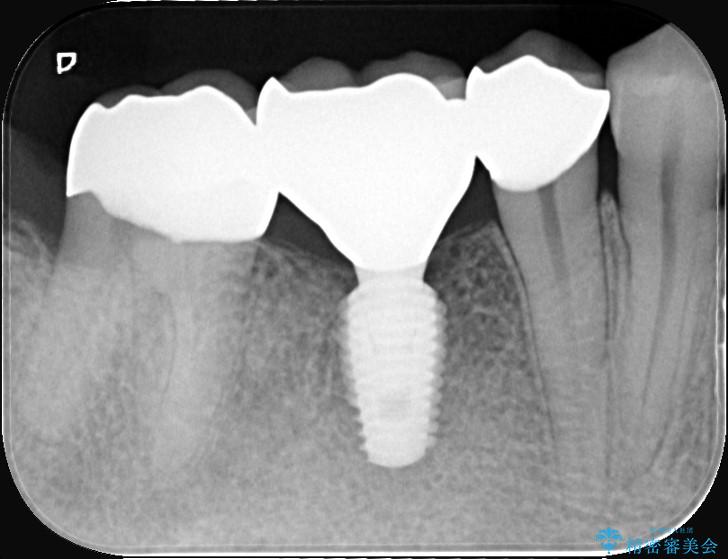

ブリッジを外し、欠損している6番にインプラントを埋入。土台となっていた5番と7番は、セラミッククラウンで修復。

インプラント周囲の歯肉が薄かったため、FGG(遊離歯肉移植術)を行い、長期安定に不可欠な「角化歯肉」を確保しました。

FGG(遊離歯肉移植術)の実施: インプラントを長持ちさせるためには、周囲に硬く動かない「角化歯肉」が必要です。患者様の上あごから丈夫な歯肉を移植するFGGを行うことで、インプラント周囲に十分な厚みと幅のある角化歯肉を形成しました。